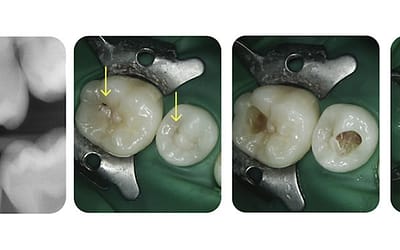

A recent case study on Dental Decay

We recently saw this 15 year old patient for a check-up and identified possible signs of tooth decay. Following an X-Ray, it was clear that there was significant tooth decay and caries needing...